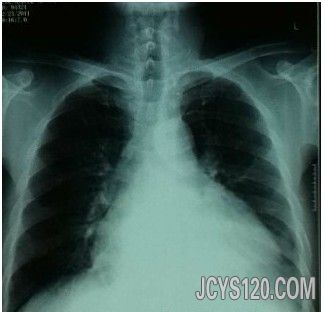

• 胸闷乏力3年,呼吸困难心悸10天。 attach_img agree

• 患者男,60岁,胸闷乏力3年,呼吸困难心悸10天。 该患者于三年前一次体力活动后,自觉胸闷乏力,经休息后减轻,从此以后身体大不如前,身体免疫力也下降,每年都发生几次急性上呼吸道急性炎症,发病时,在当 ...  阅读全文>